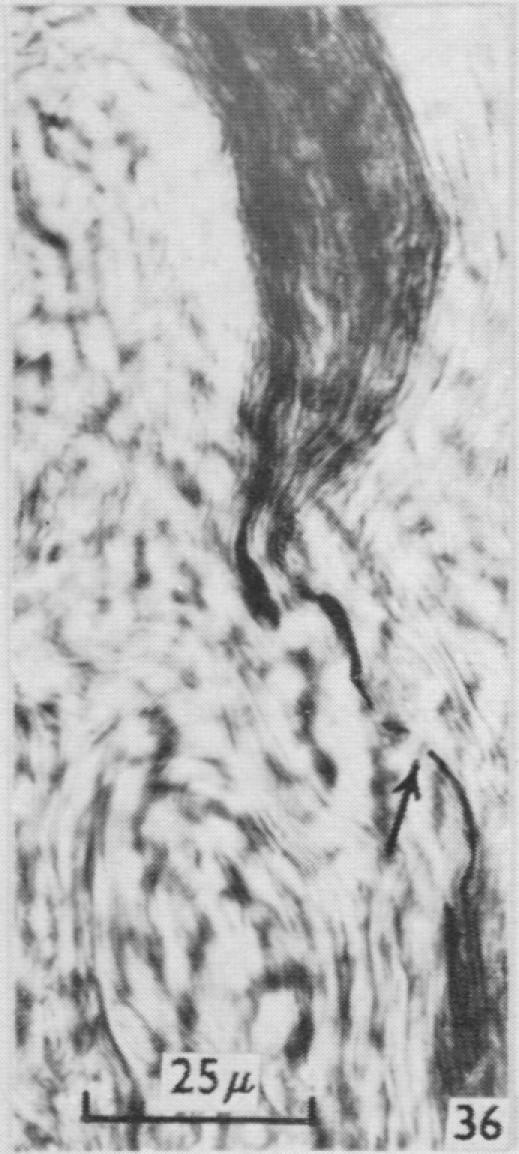

On the structure and life history of bulbous corpuscles (Corpuscula nervorum terminalia bulboidea).

https://cdn.ncbi.nlm.nih.gov/pmc/blobs/79c3/1244142/6098796426e9/janat00431-0089-a.jpg